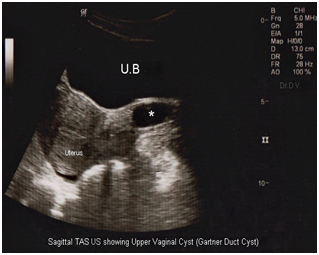

A 36 year-old woman, gravida 2 para 2, consulted our hospital outpatient department with complaints of a vaginal mass since 8 months. She gave no history of any menstrual irregularity, vaginal discharge, urinary retention, incontinence, fever, injury, and backache, abdominal or pelvic pain, excepting for some discomfort during sexual intercourse. Per speculum examination showed a large cyst 6x7x5cm in size, originating from the proximal vagina. It was pedunculated, fluctuant, non tender, mobile, cystic-like and protruding from the right anterolateral vaginal wall (Figure 1). The rest of the genitourinary and abdominal systems were without notable abnormalities and pathology. Her laboratory routine investigations were within normal limits and urinalysis and pregnancy tests were negative. Ultrasound showed a large anechoic fluid filled cyst of 6x7 cm distinct from the uterus. Sagittal transvaginal scanning (Figure 2) showed up a well- defined cystic mass on the right anterolateral aspect of the upper vaginal vault adjacent to, yet clearly separate from, the cervical tissue. Transverse transvaginal scanning confirmed these findings and delineated the cyst lateral to the uterine cervix on the right side (Figure 3). At this stage, a provisional diagnosis of a Gartner duct cyst was considered. Both maternal kidneys appeared normal.

Figure 2&3 Computed tomography demonstrated a multiloculated, cystic mass left of the vaginal cuff.